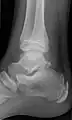

Ankle

Accessory bones at the ankle mainly include:

- Os subtibiale, with a prevalence of approximately 1%.[14] It is a secondary ossification center of the distal tibia that appears during the first year of life, and which in most people fuses with the shaft at approximately 15 years in females and approximately 17 years in males.[14]

- Os subfibulare, with a prevalence of approximately 0.2%.[15]

Os trigonum (further described below) may also be seen on an ankle X-ray.

Os trigonum

The os trigonum or accessory talus represents a failure of fusion of the lateral tubercle of the posterior process of the talus bone. Is estimated to be present in 7–25% of adults.[17] It can be mistaken for an avulsion fracture of lateral tubercle of talus (Shepherd fracture) or a fracture of the Stieda process. In most cases, Os Trigonum will go unnoticed, but with some ankle injuries it can get trapped between the heel and ankle bones which irritates the surrounding structures, leading to Os Trigonum Syndrome.[21]